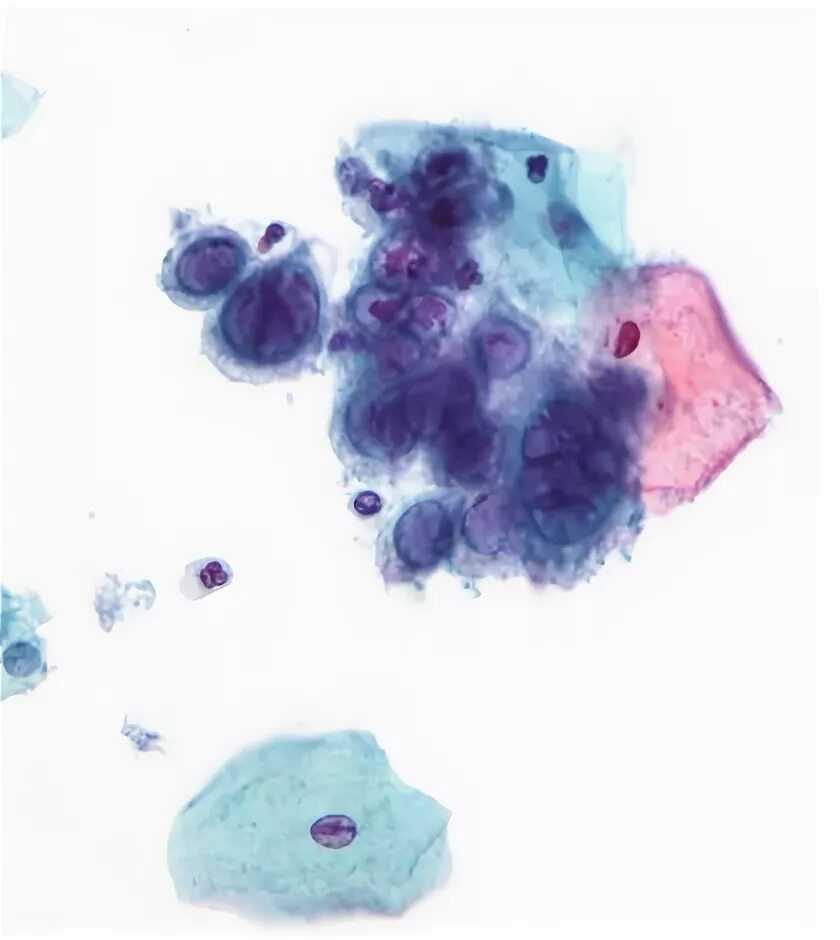

Hsv 2 тип